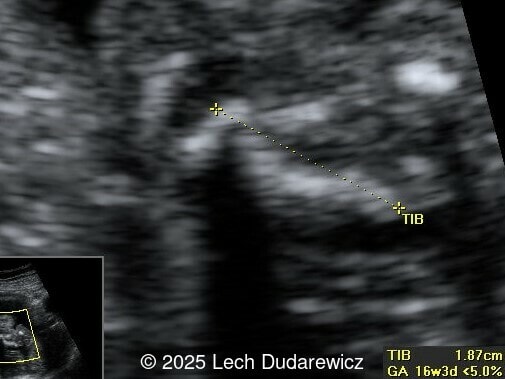

Ultrasound revealed a single live fetus with 46,XY karyotype. Biometric measurements demonstrated discrepancies with the femur and tibia length lagging significantly at 19 weeks and notable shortening and bowing of the femur, tibia, and fibula. The findings were consistent with skeletal dysplasia.

Prenatal ultrasound is a crucial tool for early diagnosis, enabling appropriate counseling and perinatal management of campomelic dysplasia. Key skeletal abnormalities include significant shortening and bowing of long bones, particularly the femur and tibia. In a study by Mansour et al, the lower extremities are primarily involved with minimal bowing of the humerus, ulna, and radius. Bowing often presents with associated angulation, giving rise to the term "campomelia," meaning bent limbs in Greek. Hypoplastic iliac bones and scapulae are hallmark features, while rib anomalies such as deformities or reduced number, typically 11 pairs, may also be observed. Additionally, the chest may be narrow and bell-shaped. Cervical spine abnormalities, including excessive lordosis or kyphosis, are often present and may contribute to postnatal respiratory complications. These findings are important for risk stratification and delivery planning.